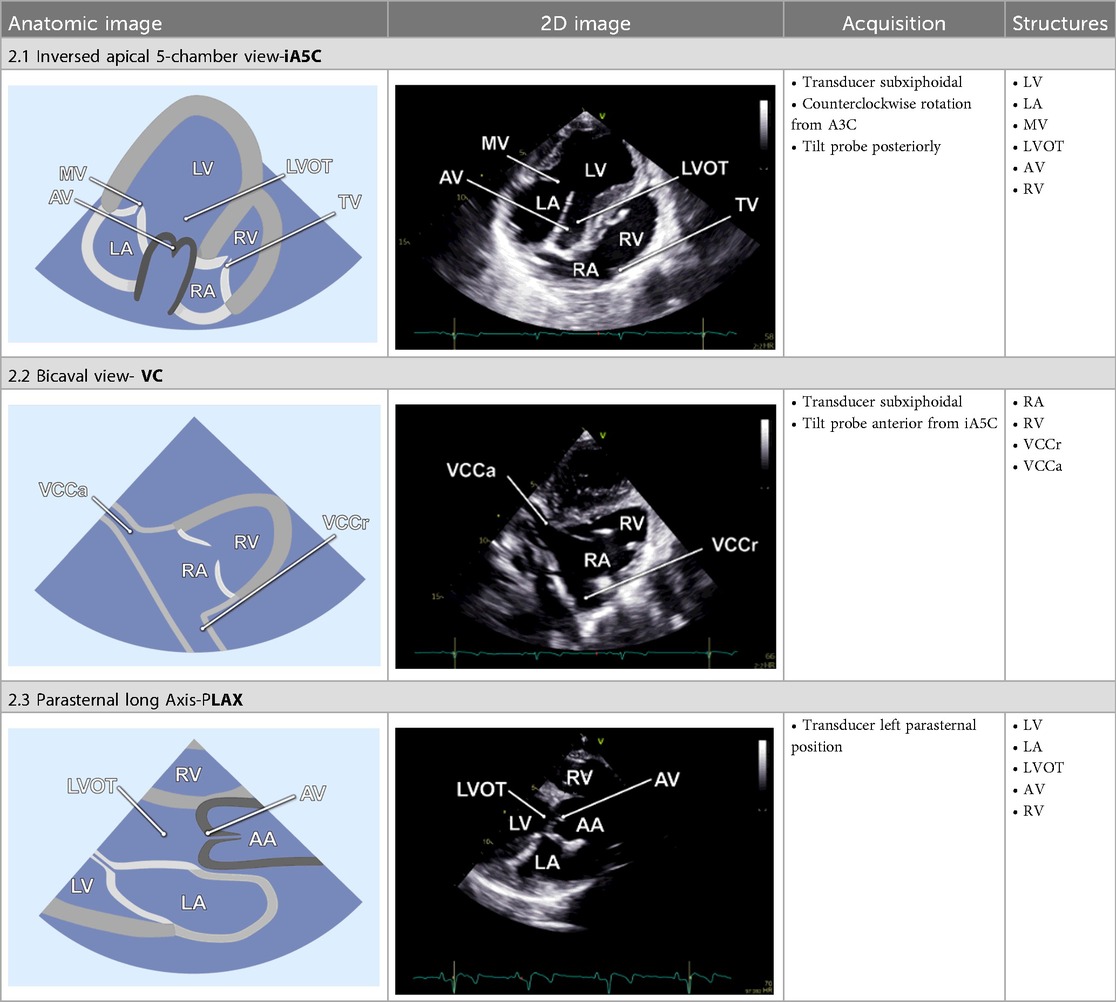

Table 2

www.frontiersin.org

Table 2. Additional two-dimensional imaging protocol for swine.

2.2.6 Inversed apical 5-chamber view

By tilting the transducer anteriorly from the A3C, the inversed 5-chamber view (iA5C) was obtained (Table 2). This view focuses on the RV and TV and partially on the LV. It served as an alternative approach for detailed assessment of the anatomy and function of the RV.

2.2.7 Bicaval view

The bicaval view (VC) was acquired by anterior tilting of the transducer from the iA5C until the right atrium entered the imaging plane. In this view, the cranial (superior) and caudal (inferior) venae cavae (Table 2) are well visualized, whereas the LV and RV appear only marginally. The VC was primarily applied to guide catheter-based procedures.

2.2.8 Parasternal long axis

The parasternal long-axis view (PLAX) was specifically utilized to measure the LVOT diameter 1–2 mm proximal to the AV leaflets during mid-systole. Therefore, the transducer was placed in the left parasternal position and the LVOT was focused (Table 2).